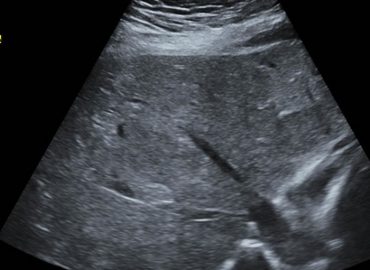

Sexo: masculino Edad: 26 años MC: dolor en región lumbar izquierda